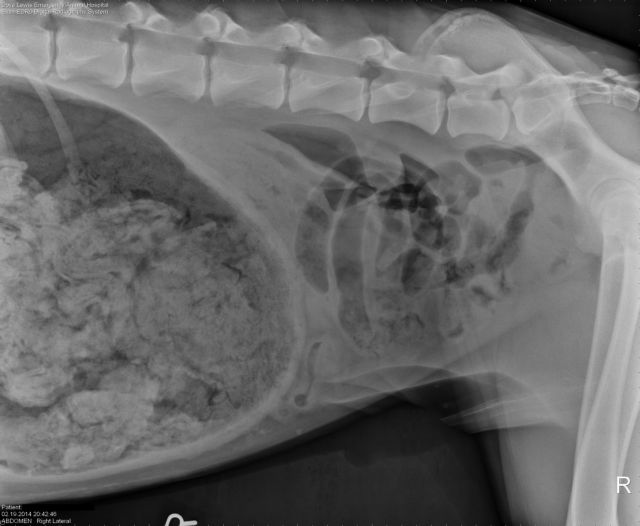

Οι ακτινογραφίες στο κατοικίδιο, ηλικίας 3 ετών, έδειξαν μια «μεγάλη ποσότητα ξένου υλικού». Έπειτα από μια επέμβαση διάρκειας σχεδόν δύο ωρών, η αλήθεια ήρθε στο φως: το σκυλί είχε καταπιεί 43,5 κάλτσες.